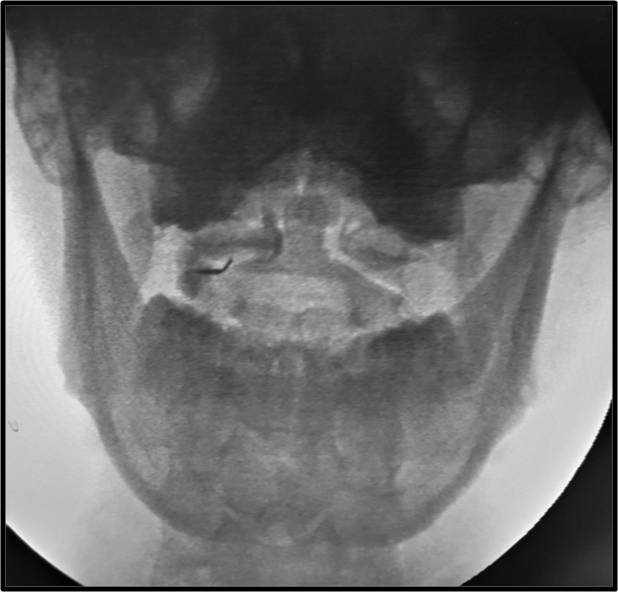

Πρόκειται για την έγχυση μικρής ποσότητας στεροειδούς στην ατλαντοϊνιακή ή στην ατλαντοαξονική άρθρωση της ανώτερης αυχενικής μοίρας κάτω από ακτινοσκοπική καθοδήγηση. Η ανάπτυξη αρθρίτιδας ή ο τραυματισμός των αρθρώσεων αυτών μπορεί να αποτελεί πηγή χρόνιου σοβαρού πόνου στην αυχενοϊνιακή χώρα.